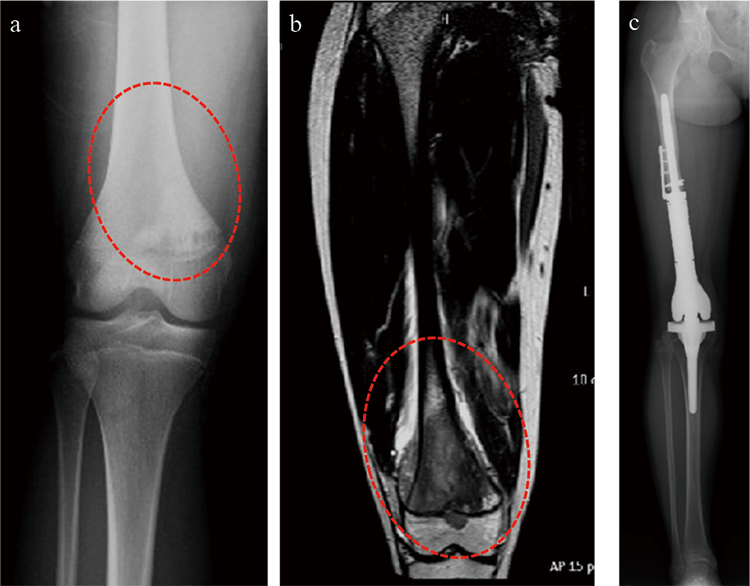

骨肉腫とユーイング肉腫の診断には、通常、X 線、 CT スキャン、 MRI スキャンなどの画像検査と、罹患した骨または組織の生検を組み合わせて行われます。血液検査は、特定の腫瘍マーカーを特定することにより診断にも役立ちます。

骨肉腫を診断するために、医療専門家は X 線検査を依頼する前に、患者の症状と病歴について質問します。骨肉腫は、星形の新しい骨の形成、白濁した塊、および表面から隆起した外側の骨層を含むコッドマン三角形として現れることがあります。

医療専門家は、MRI スキャンを使用して骨髄および追加の軟組織を詳細に観察することがあり、これは腫瘍の範囲を特定し、他の領域に転移しているかどうかを判断するのに役立ちます。